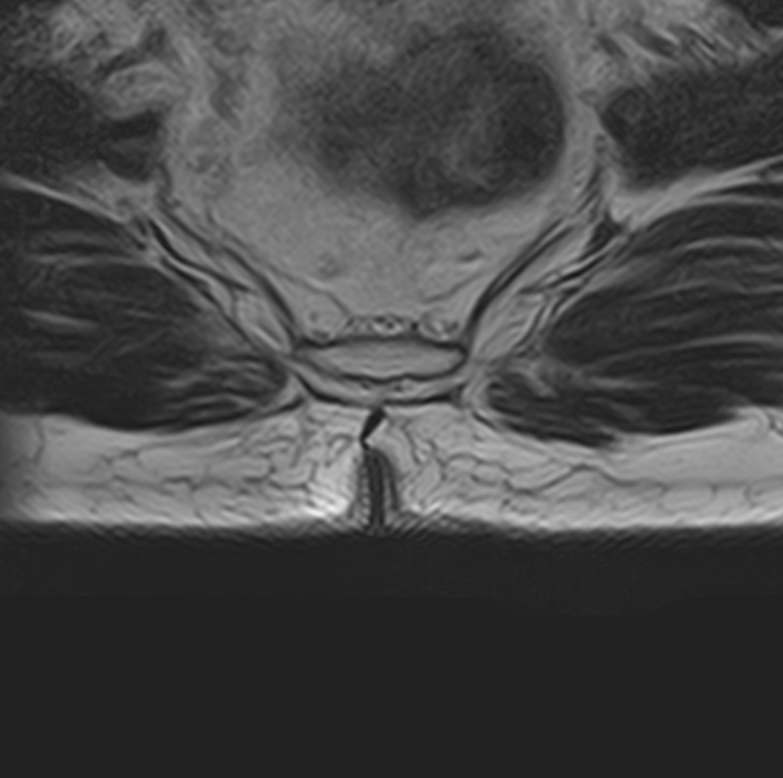

МРТ является наиболее информативным способом диагностики заболеваний позвоночника, так как позволяет оценить состояние костных структур позвонков, расположенную здесь часть спинного мозга с нервными корешками, а также связки, сухожилия и окружающие мягкие ткани. Магнитно-резонансная томография превосходит все другие методы диагностики не только по информативности, но и по безопасности, так как в основе метода лежит использование внешнего магнитного поля и отсутствует вредное для организма воздействие облучения, свойственное рентгену.